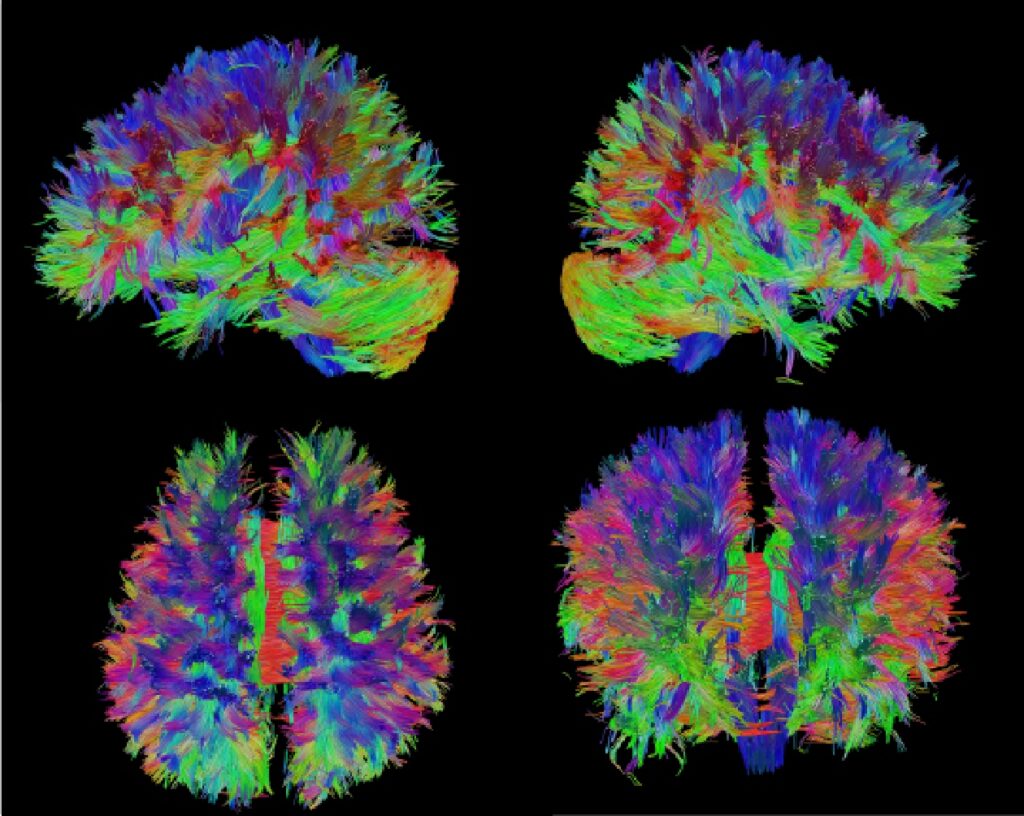

非侵襲的脳活動計測

本講座では、さまざまな脳疾患を対象とした非侵襲的脳計測手法を実施しています。これらの手法は、患者様に身体的な負担をかけずに、脳構造や活動の計測ができることが特徴です。てんかんモニタリングの一環として、頭皮脳波計測を行っており、てんかん発作時の脳波を解析し、てんかん発作のメカニズムの解明や最適な治療方針の策定に役立てています。また、臨床研究や医師主導の治験においては、本学の放射線科学講座、小児科学講座、神経内科学講座と協力し、機能的磁気共鳴画像法(fMRI)やポジトロン断層撮影(PET)を活用して、脳の特定領域の活動を可視化し、認知機能や脳疾患のメカニズム解明に取り組んでいます。